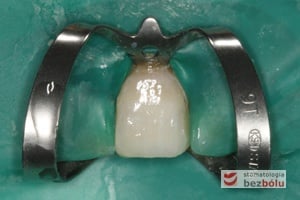

Pacjentka lat 37 zgłosiła się z silnymi dolegliwościami bólowymi siekacza centralnego na górze po stronie lewej. Ząb był w trakcie leczenia kanałowego w innej placówce. Jedno wizytowe leczenie kanałowe polegało na starannej instrumentacji kanału korzeniowego oraz wypłukaniu podchlorynem sodu, a następnie starannym odtłuszczeniu i wysuszeniu systemu korzeniowego. Kanał został szczelnie zamknięty metodą termokondensacji ciśnieniowej przy pomocy instrumentarium, tj. system B i Obtura. Kontrola radiologiczna potwierdziła szczelność wypełnienia oraz ujawniła obecność kanałów bocznych, które bez starannego wypełnienia mogłyby stać się przyczyną infekcji w obrębie wyrostka zębodołowego. Wypełnione kanały boczne przypominały dymiące fabryczne kominy. Leczenie zostało zakończone odbudowaniem zrębu koronowego z udziałem ćwieka z włókna szklanego, który został otulony materiałem kompozytowym nanohybrydowym. Jedno wizytowe sprawne leczenie endodontyczne przyniosło pacjentce natychmiastową ulgę, a odbudowa korony zredukowała ryzyko złamania zęba.